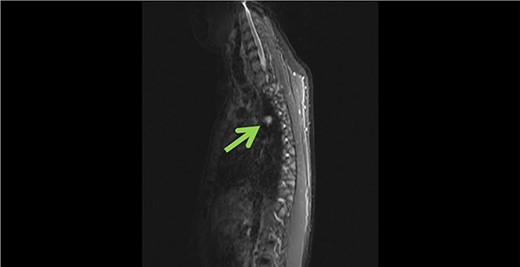

Subsequently cardiac magnetic resonance imaging (MRI) established the presence of a well-defined lobulated hyperintense HASTE lesion at the right paraspinal lesion, posterior to the carina at T4/T5 level, measuring 1.2 cm × 3.1 cm × 1.5 cm. (Figs 1 and 2) There was no regional wall motion abnormality, ventricular strain, valvular incompetency or pericardial effusion. Further contrast enhanced computed tomography (CECT) thorax with complementary MRI thoracic spine confirmed the location of the lesion, and it appeared to be in continuity with the adjacent AV. On the complementary MRI, the lesion showed isointense signal on T1, hyperintense signal on T2 and T1RM. On CINE sequence, there was continuous blood flow within this lesion to the AV. A diagnosis of AVA was made.